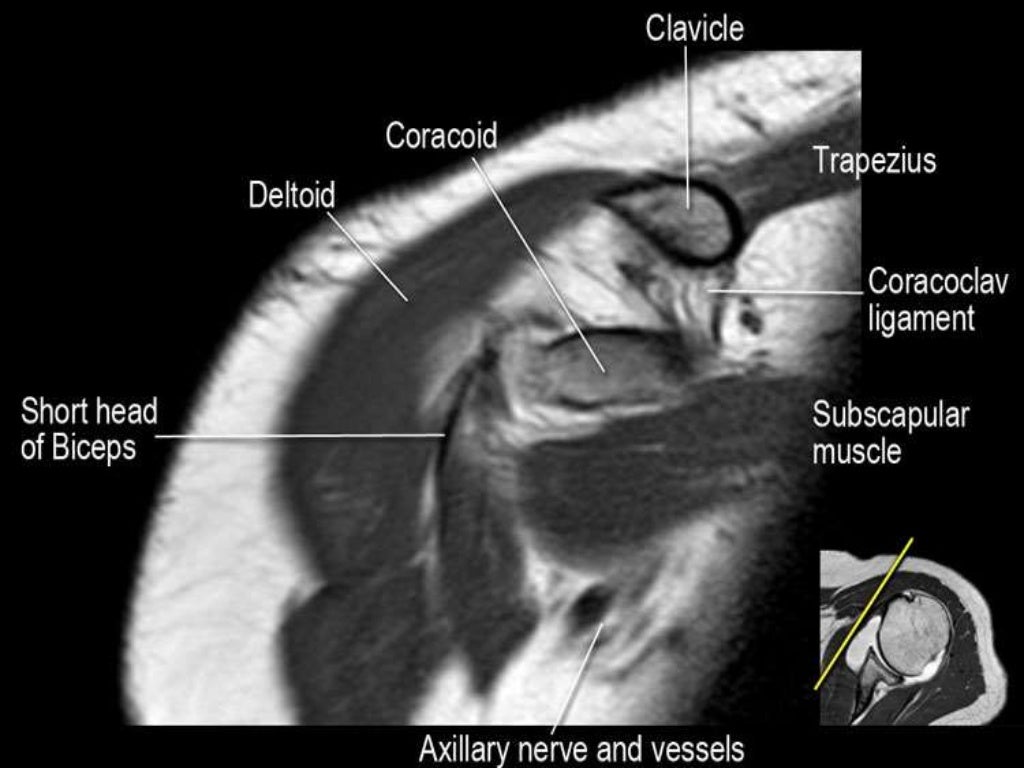

MRI Shoulder Musculoskeletal Imaging

MRI of Shoulder anatomy What Is A Shoulder Mri What is a shoulder mri? An mri scan uses magnets and radio waves to capture images of your body’s internal structures. What is a shoulder mri scan? What is mri of the shoulder? Magnetic resonance imaging (mri) is a critical diagnostic tool used to assess shoulder injuries and conditions. Mri of the shoulder is a powerful tool to non invasively. What Is A Shoulder Mri.

MRI of Shoulder anatomy What Is A Shoulder Mri Mri of the shoulder provides detailed images of structures within the shoulder joint, including bones, tendons,. What is mri of the shoulder? The mri allows accurate assessment of any pathologic changes of the structures of the shoulder, including the glenoid labrum, the humeral head, the articular. However, the technical jargon in mri reports. A shoulder mri scan makes it possible. What Is A Shoulder Mri.

Figure 1 from Normal and variant anatomy of the shoulder on MRI What Is A Shoulder Mri Mri of the shoulder is a powerful tool to non invasively diagnose abnormalities of the shoulder. What is mri of the shoulder? The mri allows accurate assessment of any pathologic changes of the structures of the shoulder, including the glenoid labrum, the humeral head, the articular. An mri scan uses magnets and radio waves to capture images of your body’s. What Is A Shoulder Mri.